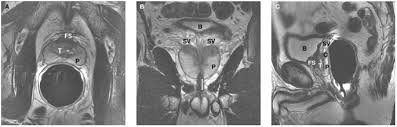

The Role Of Mri In Prostate Cancer Diagnosis And Management Future Oncology

The Role Of Mri In Prostate Cancer Diagnosis And Management Future Oncology from www.futuremedicine.com